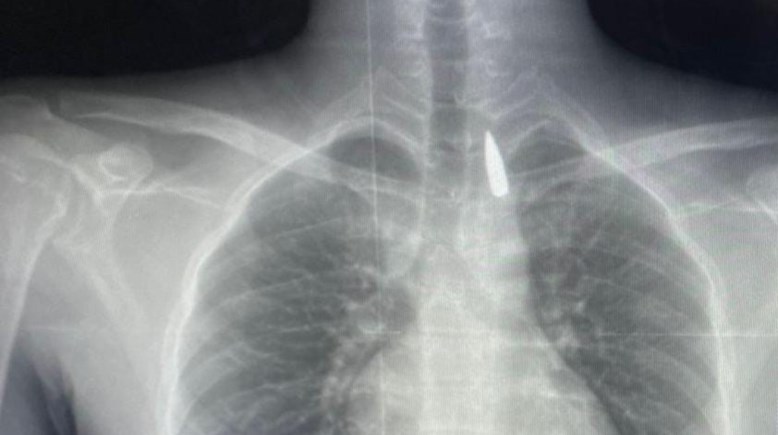

رصاصة اخترقت رأسه ووصلت لقلبه، أطباء جامعة الإسكندرية ينقذون حياة فلسطيني

استخراج رصاصة من قفص صدري